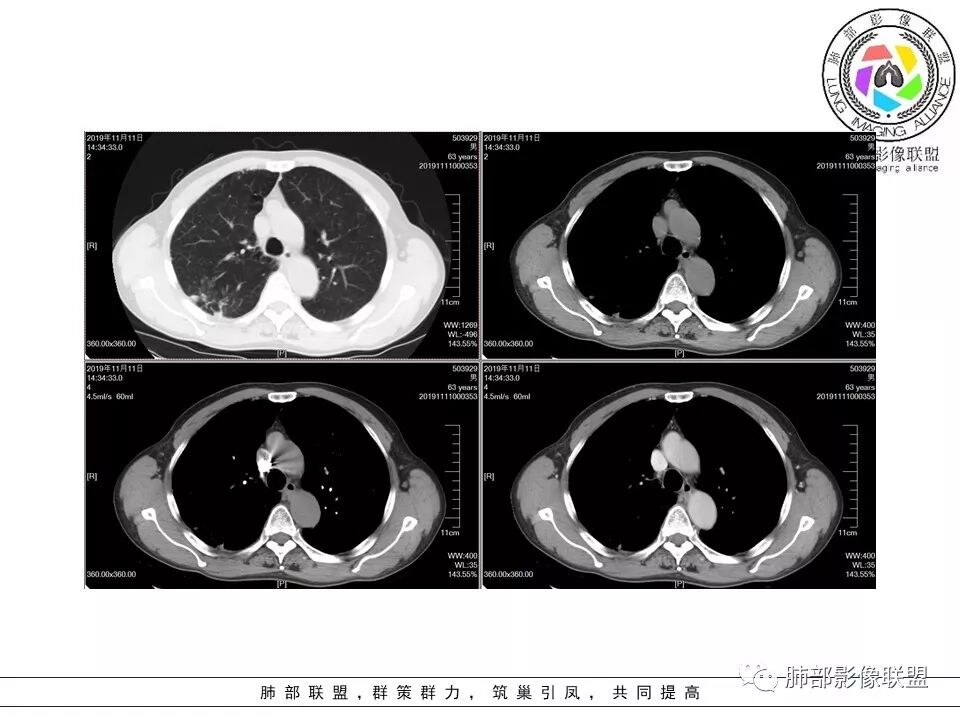

大雄:老年男性,有类风湿病史,长期服用激素,无阳性主诉CT示右肺上叶后段及左肺下叶基底段胸膜下多结节影,境界清晰,边缘毛糙,整体收缩,长轴与胸膜平行,增强扫描轻中度均匀强化。考虑炎性病变,建议查隐球荚膜多糖滴度试验

晕晕菜:患者中老年男性,体检发现肺部占位。既往既往有类风湿关节炎,长期口服激素胸CT:间隔旁肺气肿,右肺上叶后段胸膜下病变,与胸膜宽基底相连,局部胸膜明显增厚,病灶内可见空洞,病灶周围有散在卫星灶。左肺下叶背段胸膜下实变,病灶边界清楚,与长轴与胸膜平行,病灶周围可见软毛刺,纵隔窗可见病灶与胸膜呈糊墙征。 总体考虑良性病变。右上:结核?左下:隐球菌?

没意见:老年男性,明确有风免疾病背景,长期激素治疗,CT:双肺下叶外周多发结节,大部分宽基底胸膜相连,长轴垂直支气管,刀切平直,密度较为均匀,近心端空洞,强化程度目测略低,下肺背侧网格、磨玻璃、小蜂窝,考虑炎性结节,至于是感染还是风湿结节难度较大,需要结合临床来进一步确认

小赵:老年男性,类风湿及长期服药史。胸部CT所见右肺上叶及左肺下叶胸膜下多发病灶,右肺上叶病灶内见空洞及液平面,内壁光滑,周围散在条索及小结节样卫星灶,邻近胸膜增厚,增强扫描病灶轻度强化。左肺下叶病灶长轴平行于胸膜,周围见边界不清磨玻璃密度影,与邻近胸膜成糊墙改变。增强扫描病变成不均匀明显强化,内见强化血管影。诊断一元考虑双肺炎性病变,隐球菌可能。二元考虑右肺上叶结核,左肺下叶隐球菌感染,粘液腺癌待排。

菲菲菲:男,63,体检发现肺占位,既往类风湿性关节炎13年,双肺胸膜下多发斑片及结节影,右肺下叶病灶内见偏心性小空洞形成,周围有卫星灶,胸膜增厚,左肺下叶病灶轻度强化,纵隔内无肿大淋巴结,考虑炎性病变。隐球菌鉴别结核

一米阳光:双肺胸膜下多发结节病影,小结节融合,病灶与胸膜面平行,垂直支气管,边缘模糊,晕征,支气管进入堵塞,内见小空洞,增强均匀强化。结合病史,有类风湿病史,考虑炎性肉芽肿,隐球菌感染。鉴别,结核建议,穿刺,隐球荚膜抗原检查

破风5:胸部CT:右上叶胸膜下病变,与胸膜宽基底相连,累及胸膜,病灶内可见空洞,洞壁光滑,病灶周围有散在卫星灶。有类风湿激素口服历史,结核首先考虑。左肺下叶背段胸膜下实变,病灶边界清楚,与长轴与胸膜平行,血管伸入,纵隔窗可见糊墙征。考虑良性病变,隐球?总体,右上肺结核,左下肺隐球,CTD-ILD

流心明智:患者,老年男性,既往有类风湿关节炎,长期口服激素史。胸CT:间隔旁肺气肿,右肺上叶后段胸膜下病变,与胸膜宽基底相连,局部胸膜增厚,病灶内向肺门侧空洞,病灶周围卫星灶。考虑炎性病灶。左肺下叶胸膜下气肿背景边缘实变、边界清楚、有膨隆、滋养血管征,软毛刺、多结节融合、糊墙征。 总体考虑:良性病变,右上:结核?左下:隐球菌?左下鉴别Ca。

右上叶边缘收缩,宽基底与胸膜相连,胸膜增厚,附近索条,支持炎性

南边:糊墙,长轴与胸膜平行;边缘收缩+膨隆;脐凹征

常规:隐球菌与癌鉴别

脐凹征,高度提示恶性

因为其与胸膜的关系与右上叶的不一致,所以不能一元论